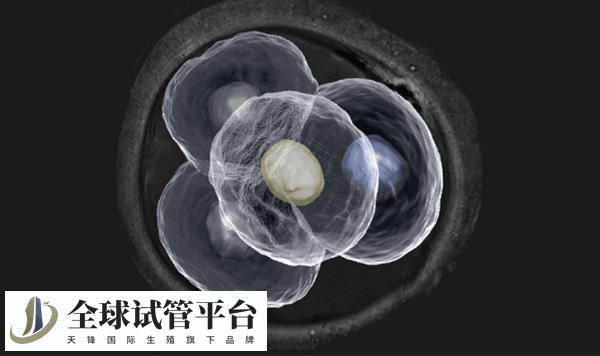

囊胚的形态

经历了早期胚胎后,等到第5、6天时胚胎会发展成上百个细胞就变成了囊胚,这时就会对囊胚应用新的评级标准而进行划分:

首先根据囊胚腔的大小和是否孵化,将囊胚的发育分为以下6个时期,不同时期囊胚的评级会不同。